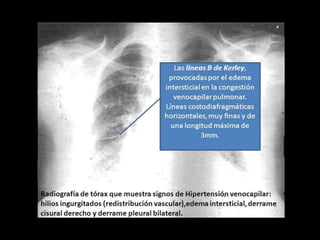

Engrosamiento vasos pulmonares